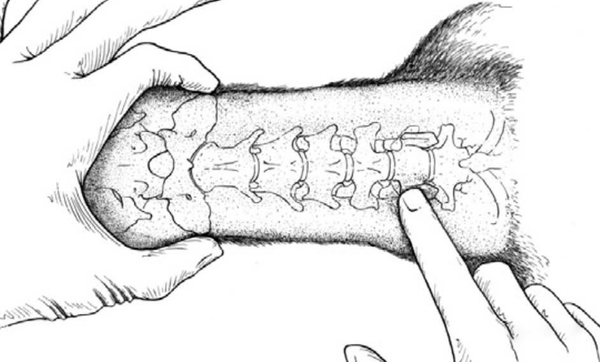

Để đảm bảo tiếp cận cột sống cổ qua đường bụng, cổ cần được cố định thẳng. Túi cát hoặc khăn được đặt dọc theo phía sau cổ để duy trì tư thế kéo dài tối đa, đồng thời hạn chế rung lắc hoặc xoay sang hai bên. Điều này giúp mở rộng không gian thao tác, tạo điều kiện thuận lợi cho việc tiếp cận và thực hiện phẫu thuật.

Trong phẫu thuật, chúng tôi xác định vị trí của đốt sống bằng cách sờ vào cánh ngang của cột sống trung tâm và mốc cánh ngang của đốt sống cổ C6. Đây là những điểm quan trọng giúp định hướng chính xác vị trí can thiệp trong quá trình phẫu thuật.